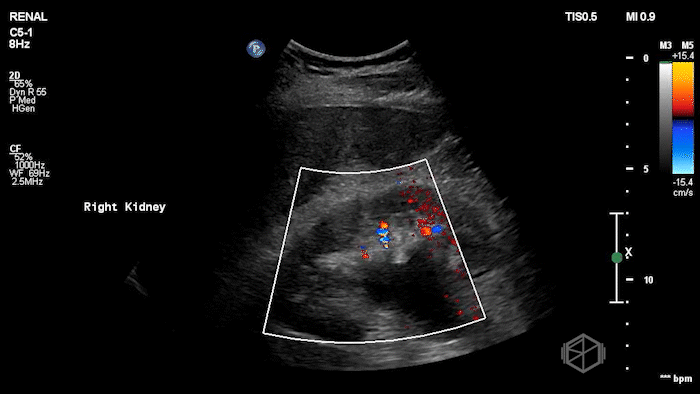

A 70's male with a history of nephrolithiasis presented to the ED with right flank pain worse over the last 4 days. Dr. Mendelow performed a POCUS immediately that showed:

Subsequent CT scanning later showed a 10 x 7 x 7mm right ureterovesical junction calculus within the urinary bladder causing moderate right hydroureteronephrosis, delayed nephrogram and mild perinephric fat stranding. The patient was taken to the OR for scope of bladder and right ureter; laser lithotripsy and removal of right ureteral stone and placement of right ureteral stent.

• Not all stones twinkle — Twinkle artifact has limitations. Doppler twinkling artifact has low sensitivity (~54%) but high specificity (~95%) for detecting urinary stones, meaning a missing twinkle does not rule a stone out

(📚 PMID: 31700749).

• Color Doppler absence of ureteral jets may suggest obstruction. Most healthy people have a ureteric jet frequency of 2 or more per minute on either side. One study reports sensitivity ~87%, specificity ~96% for detecting ureteral obstruction when less than 25% ejections are seen over five minutes, another found sensitivity to be 94.8% but specificity to be 55.5% (📚 PMID: 37465268).